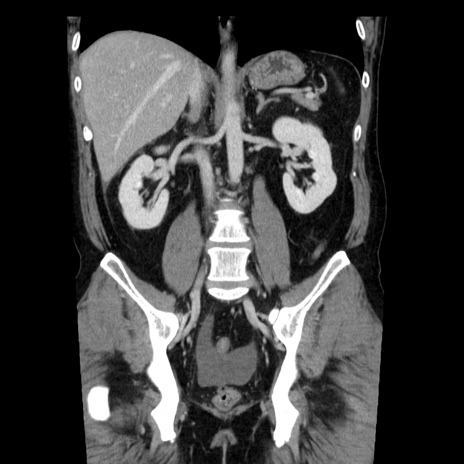

症例29(冠状断像)

【症例】40歳代男性

【現病歴】2日前から胃痛あり。徐々に周期的な激痛に変化した。本日になっても激痛があるため受診。

【身体所見】意識清明、BT 38-39℃台あり、腹部:膨満、やや硬、右下腹部に圧痛あり。

【データ】WBC 8500、CRP 23.26

横断像